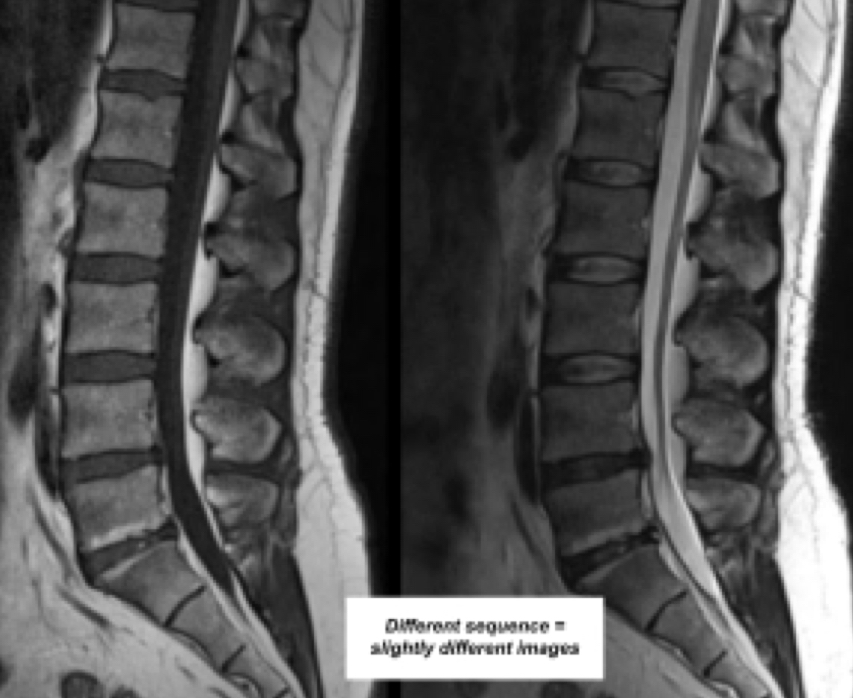

What are MRI sequences

Different programs that aid in viewing specific areas